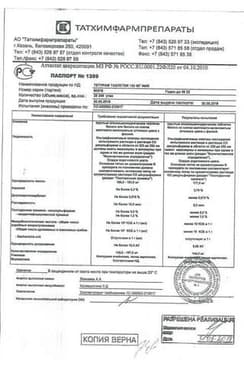

Состав препарата Тетурам

Таблетки1 таб.

дисульфирам 150 мг

30 шт. - банки полимерные (1) - пачки картонные.

10 шт. - упаковки ячейковые контурные (3) - пачки картонные.

50 шт. - банки полимерные (1) - пачки картонные.

10 шт. - упаковки ячейковые контурные (5) - пачки картонные.

30 шт. - флаконы полимерные (1) - пачки картонные.

50 шт. - флаконы полимерные (1) - пачки картонные.

Сертификаты